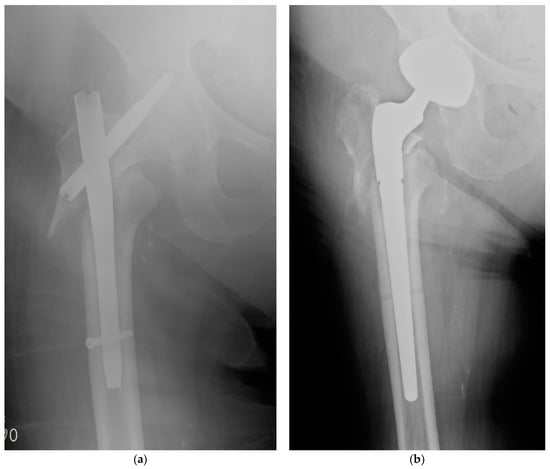

- Zagra, L.; Gallazzi, E.; Romanò, D.; Scarponi, S.; Romanò, C. Two-stage cementless hip revision for peri-prosthetic infection with an antibacterial hydrogel coating: Results of a comparative series. Int. Orthop. 2019, 43, 111–115. [Google Scholar] [CrossRef]

- Capuano, N.; Logoluso, N.; Gallazzi, E.; Drago, L.; Romanò, C.L. One-stage exchange with antibacterial hydrogel coated implants provides similar results to two-stage revision, without the coating, for the treatment of peri-prosthetic infection. Knee Surg. Sports Traumatol. Arthrosc. 2018, 26, 3362–3367. [Google Scholar] [CrossRef]

- Pellegrini, A.; Legnani, C. High rate of infection eradication following cementless one-stage revision hip arthroplasty with an antibacterial hydrogel coating. Int. J. Artif. Organs 2021, in press. [Google Scholar] [CrossRef] [PubMed]